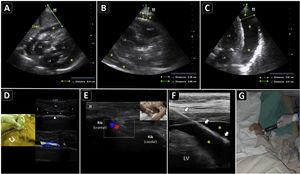

PreprocedureA convex or a phased-array probe is used to assess the view where the effusion accumulation is maximal and closest to the transducer. The thickness of the effusion is measured in diastole in each window, while the distance from the skin to the parietal pericardium and to the myocardium (visceral pericardium) should be obtained to estimate the needle depth of insertion and needle length (Fig. 2A–C). Qualitative assessment should also be performed. While anechoic fluid can be either a transudate or an exudate, the presence of debris or septations points towards the latter. Quantitative and qualitative assessments aid in decision making regarding whether pericardiocentesis, another procedure, or no procedure should be performed. Using a linear probe, the pleura, internal thoracic vessels, and intercostal vessels are delineated to exclude these structures from the needle trajectory (Fig. 2D, E.50

Ultrasound-guided pericardiocentesis. A) Subcostal 4 chamber view. B) Parasternal long-axis view. C) Apical view. As noted, the optimal window to insert the needle is the apical, given the shorter distance to reach the pericardial space (continuous green line) and higher pericardial fluid thickness (continuous yellow line). RA, right atrium; RV, right ventricle; LA, left atrium; LV, left ventricle; RVOT, right ventricular outflow tract. Asterisks indicate pericardial effusion. Adapted from Blanco P, Figueroa L, Menéndez MF, Berrueta B. Pericardiocentesis: ultrasound guidance is essential. Ultrasound J. 2022;14(1):9. https://theultrasoundjournal.springeropen.com/articles/10.1186/s13089-022-00259-5. (CC-BY-4.0). D) Recognition of the left internal thoracic vessels along the left parasternal line (dotted white line) with a linear probe on two-dimensional and color Doppler imaging; s-sct, skin-subcutaneous tissue; m, intercostal muscle; r, rib; arrowhead, pleura; asterisks, internal thoracic vessels. E) Recognition of the intercostal vessels with a linear probe on color Doppler imaging. Real-time in-plane ultrasound-guided pericardiocentesis via intercostal approach (apical view) using a linear probe. The needle (arrows) is entirely observed in the pericardial space (asterisks); LV: left ventricle. G) Hemorrhagic fluid is freely evacuated from the pericardial space after catheter placement.

A phased-array probe or convex probe is chosen to guide the procedure. Wherever possible, a linear probe aids in the best observation of the needle, particularly in intercostal pericardiocentesis (Fig. 2F). The entire intervention is performed under full sterile barrier precautions.

After disinfecting and infiltrating the target site with local anesthetics, the needle is inserted in-plane into the pericardial cavity; after aspiration a few milliliters of pericardial fluid, 5 ml of agitated saline are injected through the needle. The immediate appearance of echo contrast in the pericardial space confirms that the needle is in the pericardial cavity and rules out a cardiac chamber perforation51(Video 3). The guidewire is then passed and observed in the pericardial space, and, after dilation, the catheter is finally accommodated (Fig. 2G) and connected to a three-way stopcock and a drainage system.

PosprocedureRechecking lung sliding is mandatory when using an intercostal approach. If catheter drainage function is optimal, serial ultrasound assessments will show a reduction in the amount of pericardial fluid. When using the subcostal approach, the liver should be observed for a hematoma, and the presence of free peritoneal fluid should also be assessed.